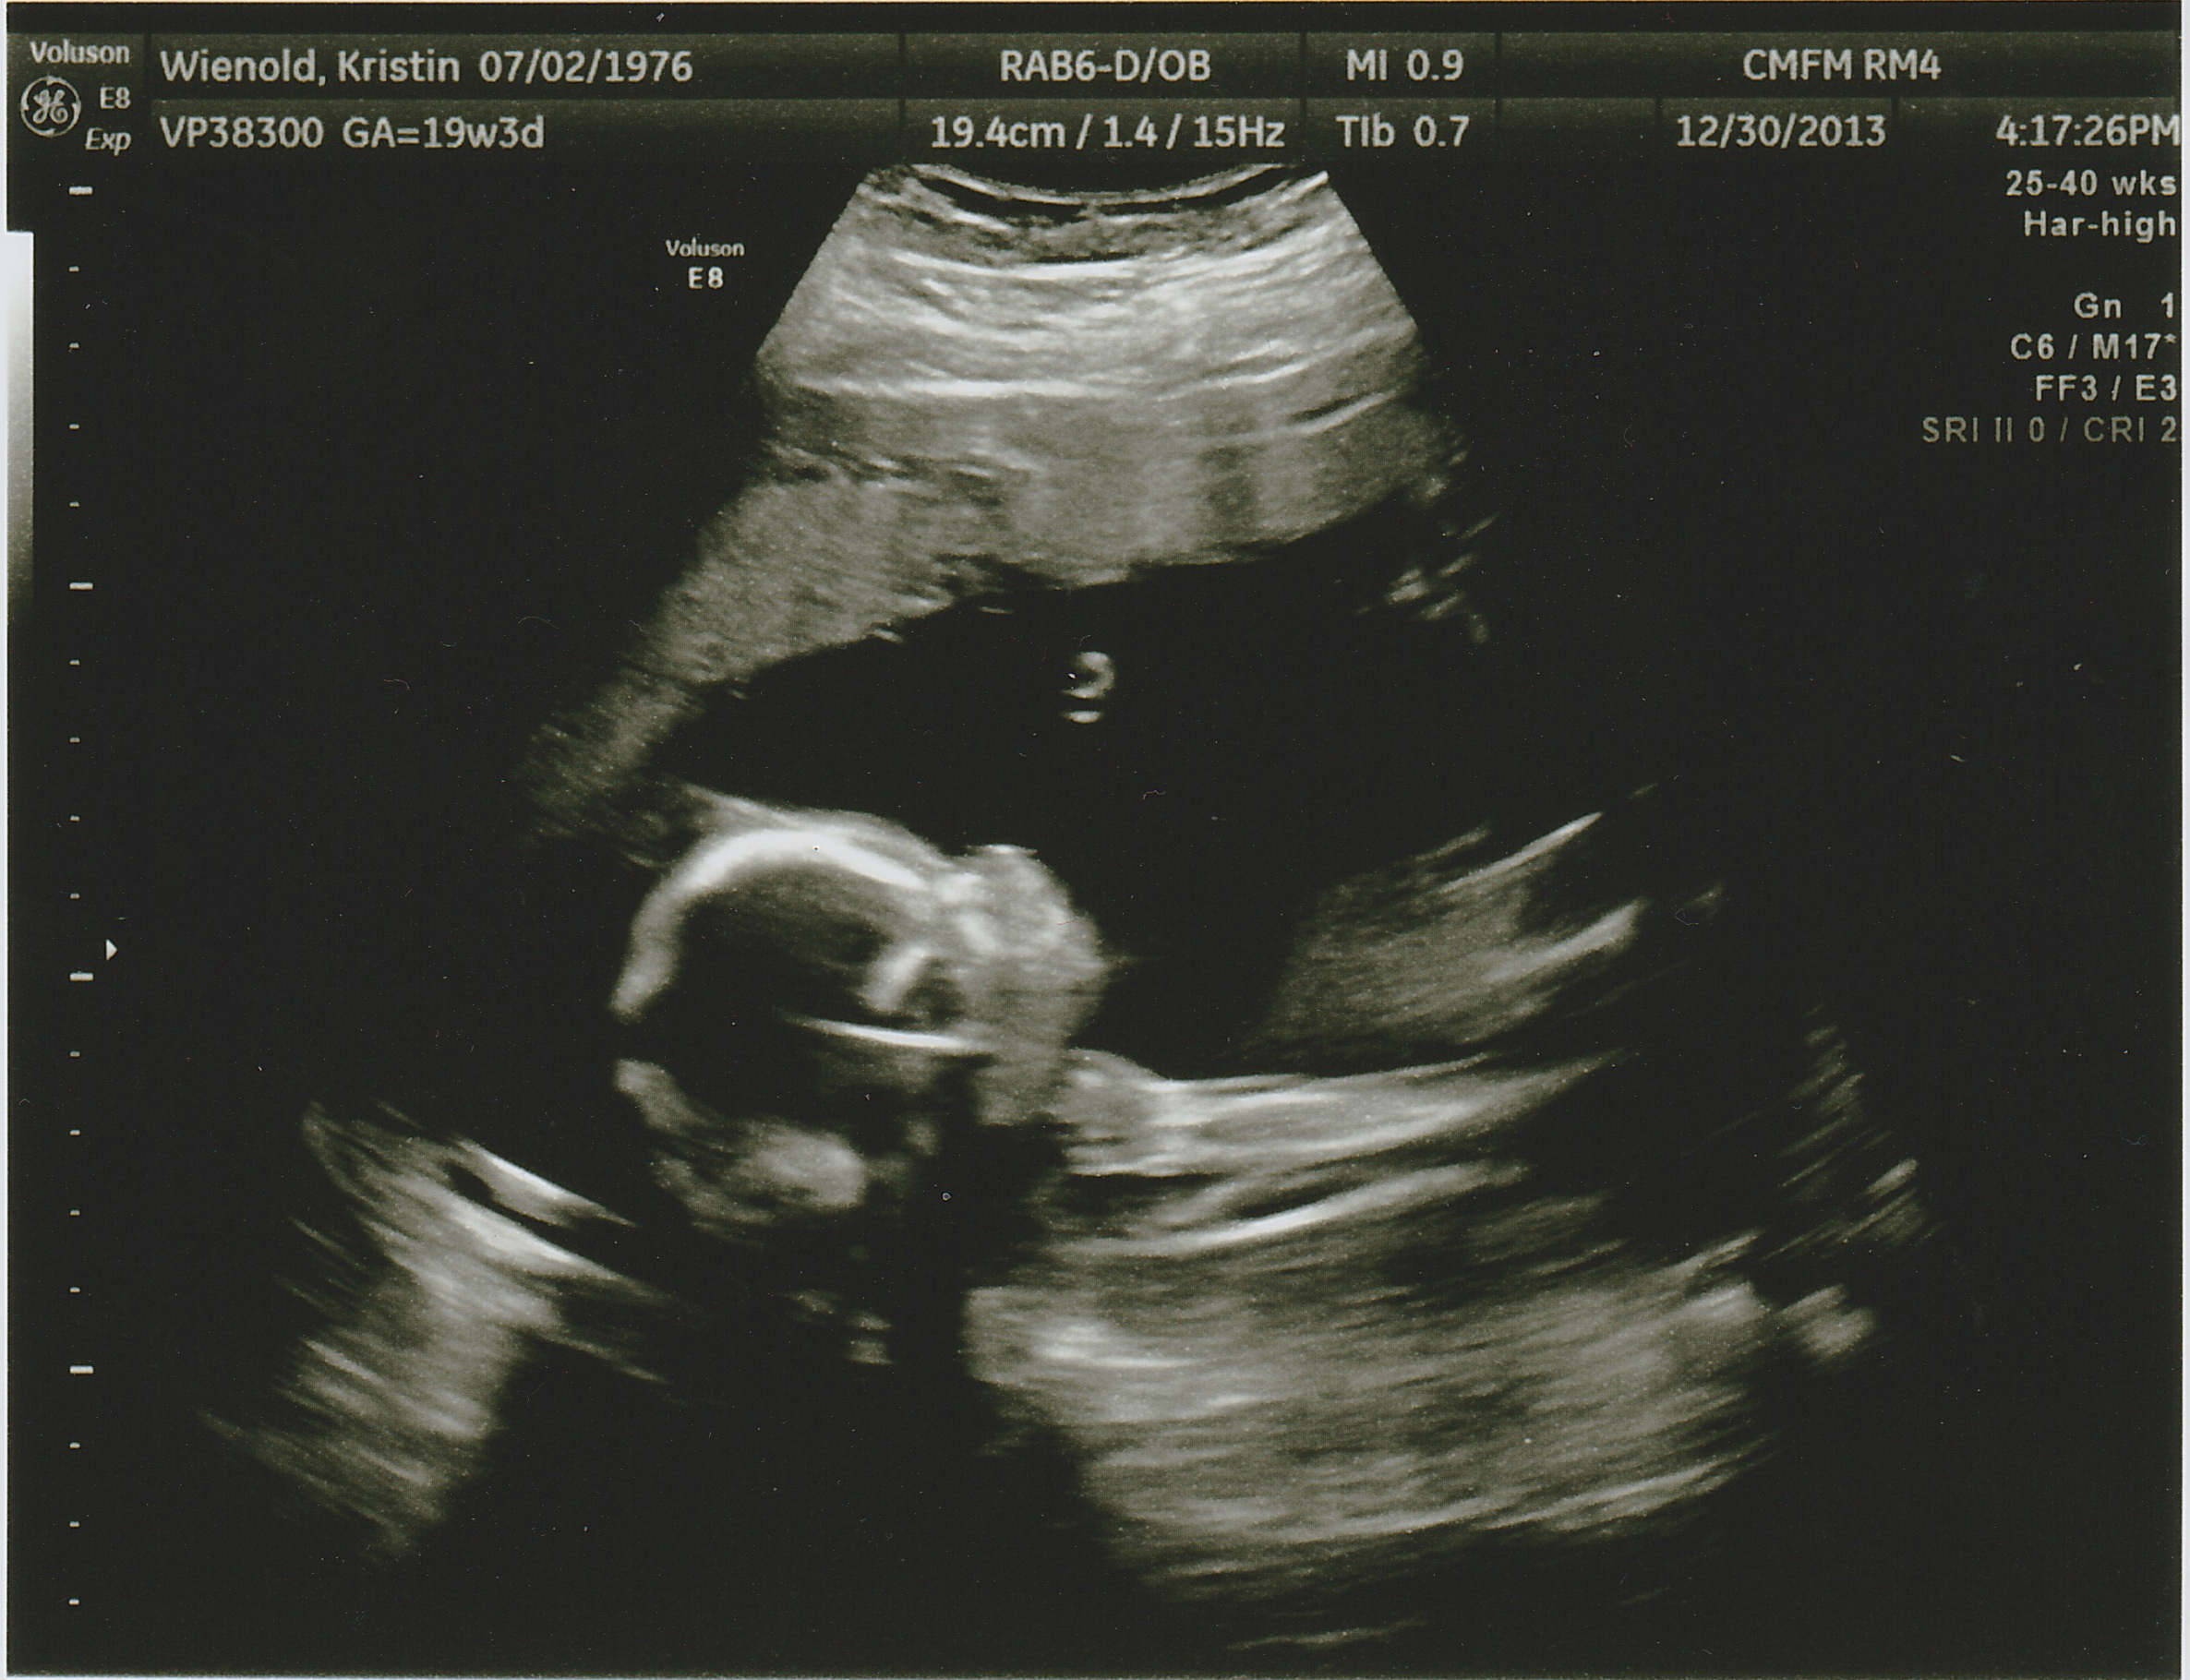

Yep… There’s a baby in there. “JP” as we call him will be here May 21st of 2014 and we simply could not be more excited. One of the constant questions we have gotten throughout the pregnancy is have you chosen a name yet? Well yes, we have… But we’re not going to tell you. Most folks are not that surprised with this response, except of course for Kris’ mom. It drives her crazy not to know. Out of this world bat-shit crazy. So J for John, P for Paul, the grandpas to be, was the suggestion by Lois. John-Paul, being rather papal, is about as likely as naming him Tire Iron or Cash Register, so its been fun to play along and tease dear grandma to be… That she will know as soon as everybody else does, what JPs real name is.